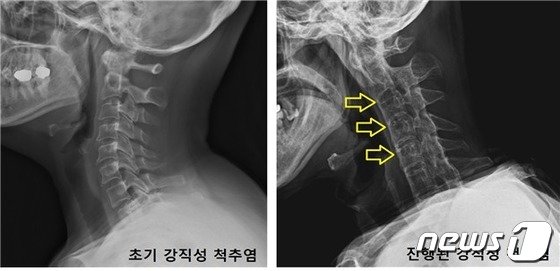

강직성 척추염 자료 (국민건강보험공단 제공)

김재민 교수는 “치료하지 않고 방치할 경우 척추 아래쪽에서 시작된 증상과 통증이 상부로 점차 진행되고, 결국 척추 변형과 강직 현상이 나타난다”며 “일상적으로 몸을 앞이나 옆으로 구부리거나 뒤쪽으로 젖히는 동작까지 어렵게 된다”고 강조했다.